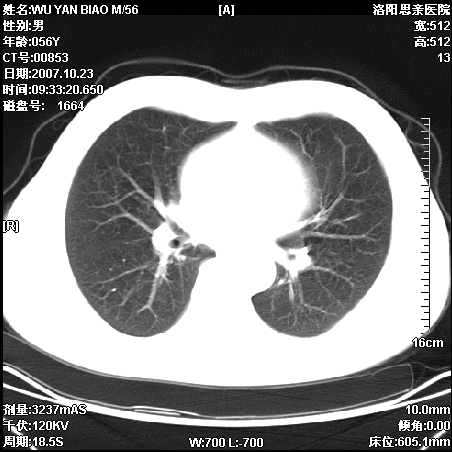

标题: CT10160:M56Y,体检发现,病人无不适,病人随访中 [打印本页]

标题: CT10160:M56Y,体检发现,病人无不适,病人随访中

后上纵隔占位,与肺交界清,宽基底附着脊柱,密度均匀,局部骨质无明确改变.

考虑;神经源性肿瘤,---起源交感n链?,不除外肠源性囊肿.

1、病灶在后纵隔脊柱旁沟内,此处是神经原性肿瘤的好发部位

2、病灶边缘光滑整齐,更说明病灶来于纵隔,由于有胸膜的包裹所以才导致这么光滑的边缘

3、病灶内的密度均匀